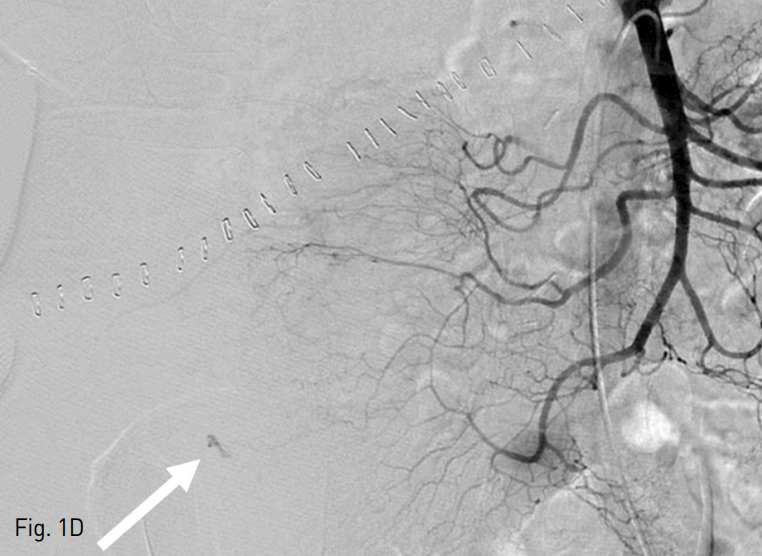

Fig. 1. A 75-year-old man with Jackson-Pratt catheter tract bleeding after radical excision of right kidney.

D. A superior mesenteric arteriogram revealed the bleeding focus (arrow) which was supplied by the right colic artery.